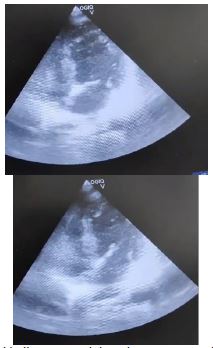

A 62-year-old postmenopausal woman with normal ECG (Figure 4) and ECHO, a k/c/o buccal mucosa carcinoma underwent a composite resection and fibular free flap under general anesthesia. The surgery was uneventful, but due to its prolonged duration and shared airway, she was put on the mechanical ventilator.

Arterial blood gas analysis revealed metabolic acidosis with elevated lactate levels. A bedside POCUS (Point-of-Care UltraSound) was performed, which showed apical ballooning and apical hypokinesia, indicating left ventricular dysfunction with an ejection fraction of 40%, later confirmed by the cardiologist (Figure 5).

Chest X-ray on the postoperative day is shown in Figure 6.

Figure 5: Apical ballooning with hypokinesia in apical 4-chamber view.

Figure 6: Shows a clear lung field.